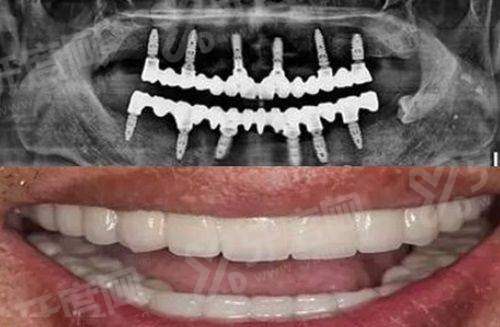

1、丹阳金铂利口腔医院张渊医生:种植技术院长,15年专注种牙,累计植入种植体8000+颗,专攻即刻种植、全口半口无牙颌即刻负重、前牙美学区种植,对骨量重度不足的上颌窦内外提升、onlay植骨有独到见解。